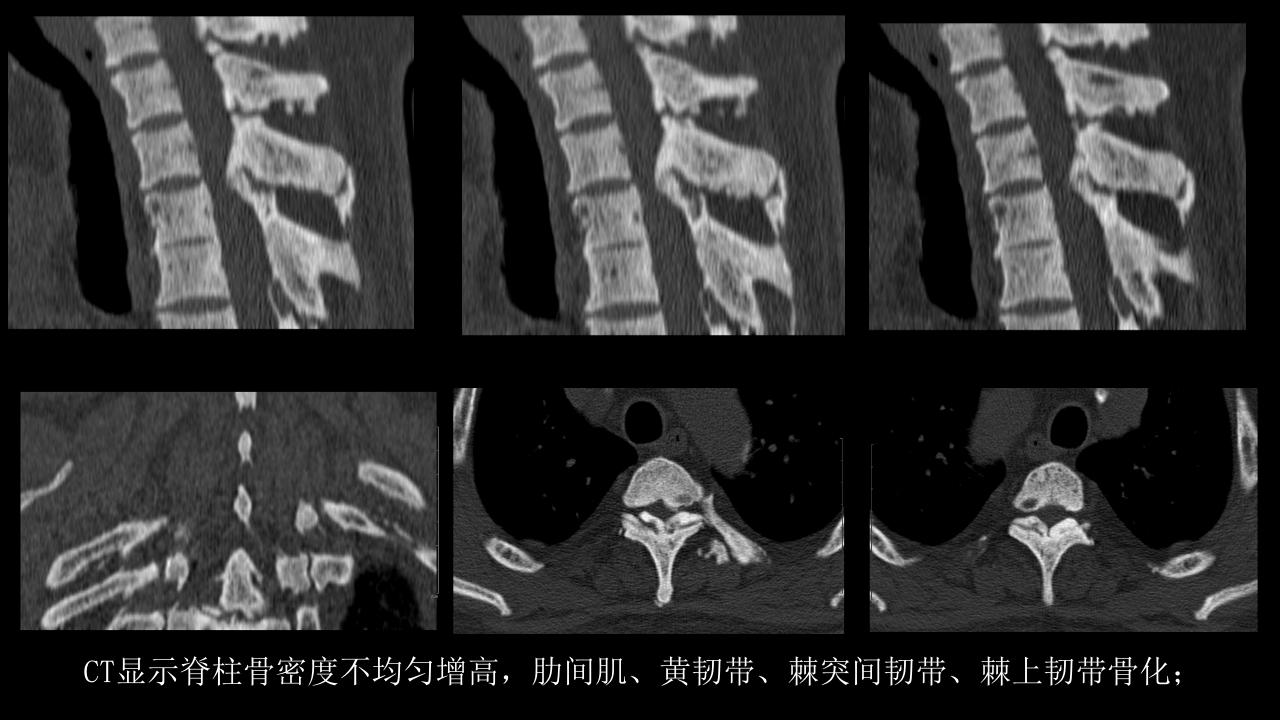

氟骨症的X线CT及MR影像及解读